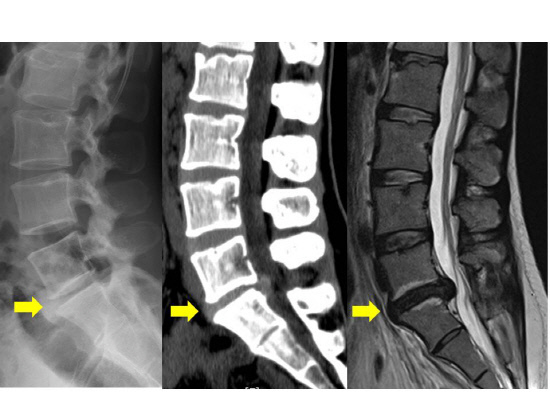

X-Ray 검사는 척추 질환을 진단하는 데 가장 기본적으로 쓰이는 검사로서 척추의 전반적인 형태를 한 눈에 볼 수 있습니다. 뼈의 모양을 여러 각도에서 촬영하므로 척추의 구조적인 형태를 관찰하기 쉽습니다. 척추측만증이나 척추분리증 등의 질환은 X-Ray 검사만으로도 확진이 가능합니다. X-Ray 검사를 통해 아래 그림처럼 뼈의 간격을 보고 퇴행성 진행정도를 먼저 파악하는 것이 중요합니다. 다만 디스크 질환은 다릅니다. 척추 뼈의 간격이나 퇴행성 진행 정도로 디스크의 가능성은 알 수 있지만, 디스크가 보이지 않기 때문에 디스크가 발생한 정확한 부위나 진행 정도를 알아내지 못해 디스크라는 확진을 내리기엔 부족합니다.

허리디스크 확진을 받으려면 엑스레이만 가지고는 안 되고, CT나 MRI 검사를 반드시 시행해야 합니다. 엑스레이를 찍은 후 허리디스크 진단을 받으면 대개 약 복용과 물리치료를 하게 되는데요. 치료를 1~2주 이상 시행해도 통증에 전혀 호전이 없거나 견딜 수 없을 정도로 극심한 통증을 느낀다면, 참지 말고 그 즉시 정밀검사를 받으러 가세요.

가끔 엑스레이만 찍고 신경주사치료를 받는 경우가 있는데, 이는 대충 여기쯤에 병이 있겠지 하고 짐작하여 치료하는 것이기 때문에 치료 효과가 떨어집니다. 허리디스크가 의심되면 CT나 MRI 검사를 시행하여 허리디스크가 어디에 생겼는지 정확한 진단을 받은 후 신경주사치료를 받는 것이 좋습니다.

대부분의 허리디스크 탈출이나 파열은 CT 검사를 통해 진단할 수 있지요. 하지만 CT 검사를 시행해도 허리디스크를 제대로 진단하지 못하는 경우가 종종 있습니다. 또한 CT 검사는 허리디스크에 눌린 신경이 어떤 상태인지 정확하게 알아낼 수 없다는 단점을 가지고 있습니다.

필자가 MRI를 환자분들께 권해드리는 이유가 여기에 있습니다. MRI는 허리디스크를 가장 정밀하게 진단하는 검사입니다. MRI 검사를 하면 허리디스크 탈출 또는 파열 여부와 신경의 상태를 가장 정확하게 진단할 수 있습니다. CT 검사에서 놓쳤던 부분들까지 MRI는 잡아준답니다. MRI는 고가의 검사이니, 환자분들이 머뭇거리게 되는 게 당연합니다.

하지만 허리디스크는 병이 있는 곳을 정확하게 찾아서, 그 근본적인 원인을 치료해야만 제대로 나을 수 있습니다. 정확한 원인을 알지 못해 문제가 없는 곳에 쓸 데 없는 치료를 하게 된다면, 시간도 비용도 건강도 오히려 더 많이 잃게 됩니다. 빠르고 건강한 치료를 위해서라면 MRI를 통해 제대로 진단하시길 권합니다.